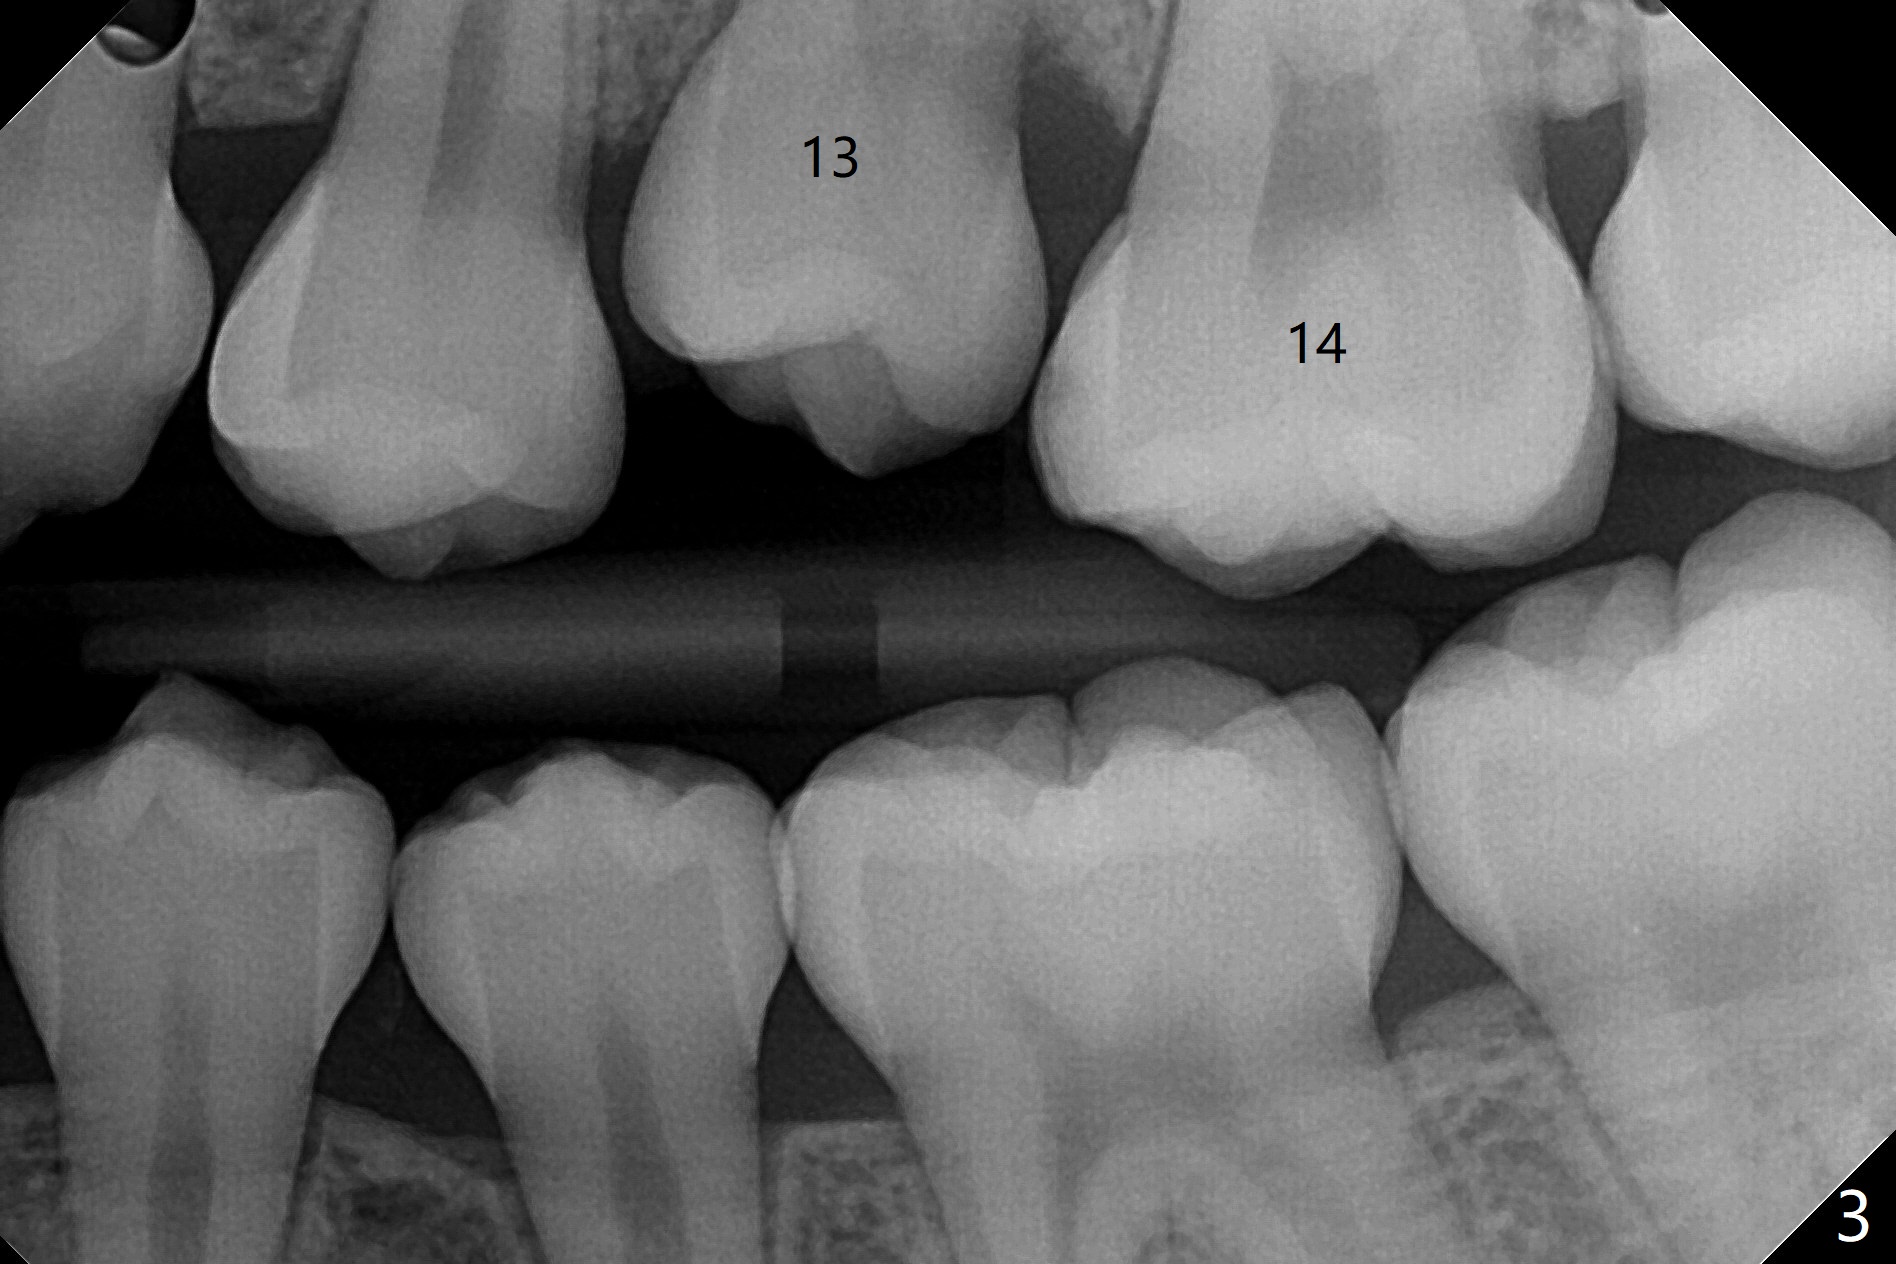

10岁半女孩上颌第二乳磨牙远中龋好像造成第一恒磨牙近中龋(图一)。要求妈妈当乳磨牙脱落时,带她回来补牙。由于新冠病毒,女孩1年3个月后才回来,右上第二前磨牙已经基本完成萌出,右上6近中龋被掩盖了(图二),而左侧前磨牙腭侧部分萌出(图三,四),磨牙近中龋(表现为脱钙,图四:箭头)正好暴露。塞入gingival retraction cord(图五:C)和wedge (W),去龋,填入树脂,两牙之间通过牙线(F),光固化。之后不需要抛光。